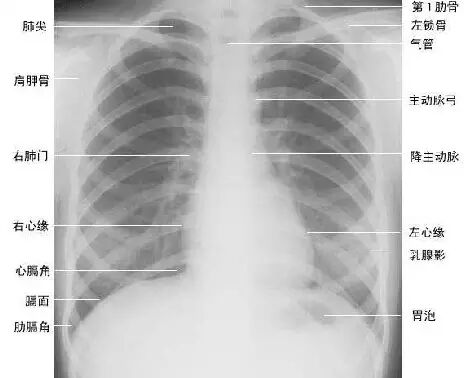

临床拍标准的胸部正位片其实是后前位片,如上图。

上图为正常胸部后前位片

下面为大家依次介绍胸部正常X线解剖

2. 肺纹理

肺纹理为自肺门向肺野呈放射状分布的树枝状阴影,它主要是肺动脉的投影,肺静脉、支气管和淋巴管也参与形成。肺纹理由肺门向外围延伸,逐渐变细,至肺野外带渐细小而稀少,距侧胸壁内缘约1cm范围内的肺野基本无肺纹理可见(图下图)。

3. 肺野、肺带的划分

纵隔两旁含气的肺在胸片上所显示的透明区域称肺野,其透明度随呼吸而改变,深吸气时肺内含气量增多,透明度增高,呼气时则相反。

为便于指明病变的部位,通常人为地将一侧肺野纵向分为三等分,即内、中、外带。又分别在两侧第2、4肋骨前端下缘划一水平线,将肺野横向分为上、中、下三个肺野。(如上图)。

7.胸廓

正常胸廓由软组织与骨骼组成,两侧对称。

①骨性结构: 肋骨、锁骨、肩胛骨、胸椎

②软组织结构:胸锁乳头肌、锁骨上皮肤皱褶、胸大肌、女性乳房 / 乳头